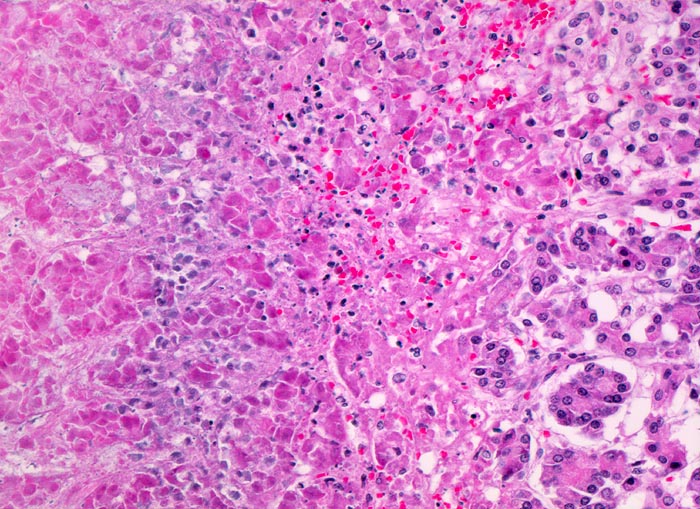

Das Spektrum reicht von Ödem und Infiltraten neutrophiler Granulozyten ohne oder mit kleinen Fettgewebsnekrosen bei der interstitiell-ödematösen Variante über großflächige hämorrhagische Nekrosen im peripankreatischen Fettgewebe und im Pankreasparenchym bei der nekrotisch-hämorrhagischen Variante (Kurspräparat). Das peripankreatische Fettgewebe wird bei der nekrotisch-hämorrhagischen Variante durchsetzt von grösseren Fettgewebsnekrosen mit Verseifung, die gesäumt werden von dichten Infiltraten neutrophiler Granulozyten teils mit Abszessbildung. Die Hämorrhagien kommen durch Wandnekrosen kleiner und mittelgrosser Venen im peripankreatischen Fettgewebe zustande.

Bei beiden Varianten der akuten Pankreatitis ist das entzündliche Infiltrat zu Beginn der Erkrankung durch neutrophile Granulozyten dominiert. In der Organisationsphase kommen Makrophagen und Lymphozyten hinzu.

• Unregelmässige Nekrosestrassen durchziehen Fettgewebe und Pankreasparenchym.

• Die Grenzen zwischen vitalem und nekrotischem Gewebe sind unscharf.

• Frische, teils hämorrhagische autodigestive Kolliquationsnekrosen von Pankreasparenchym und Fettgewebe demarkiert von zerfallenden neutrophilen Granulozyten.

• Innerhalb der Nekroseareale Ablagerungen von amorphem gelborangem Hämatoidin (eisenfreies extrazelluläres Hämoglobinabbauprodukt).

• Nachweis kokkoider und fadenförmiger Bakterien im nekrotischen Fettgewebe. Das sollte der Kliniker dem Pathologen mitteilen: